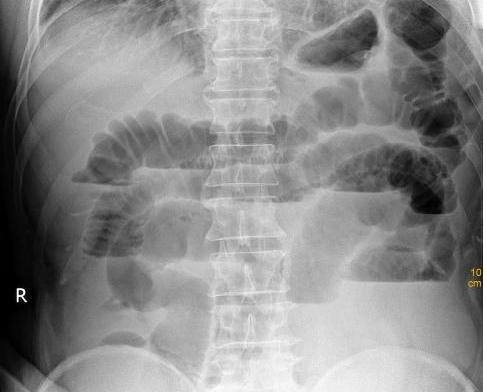

器质性的便秘的原因,常为部分性肠梗阻,如结肠肿瘤,肠粘连,炎症或赘生性狭窄等,以致便秘;肠道外疾病压迫肠道,;直肠肛门疾患,如炎症,肛裂,痔疮等;均可致肛门扩约肌痉挛而致便秘。

当肿瘤堵塞在肠道中,粪便和肠内容物不能通过时会引起消化道梗阻,使肠道功能发生紊乱。继而腹痛、腹胀随之袭来。但是,这种疼痛并不剧烈,表现为胀痛或隐痛,逐渐加重。

一半以上的肠癌患者可摸到腹部包块,这个包块是由肿瘤和周边的网膜、组织粘连形成的肿块,质地较硬,不规则大小。有些包块早期时可跟着肠管活动,晚期则完全固定。